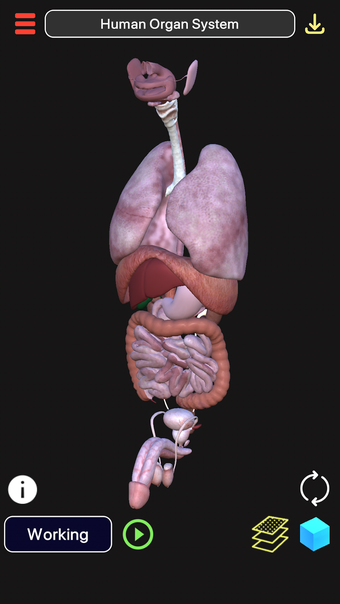

3D 생물학은 인체, 특히 생물학에 대해 배울 수 있는 무료 교육 앱입니다. 이 앱은 정보, 시각화 및 상호 작용 학습을 제공하기 위해 학생과 교사 모두를 위해 설계되었습니다.

이 앱은 3D 모델링 및 애니메이션 기술로 구축되었습니다. 오프라인 및 온라인 모드에서 모두 작동하도록 설계되었습니다. 오프라인 모드에서는 미리 다운로드 된 모델을 볼 수 있고, 온라인 모드에서는 온라인 라이브러리에서 새로운 모델을 다운로드 할 수 있습니다.